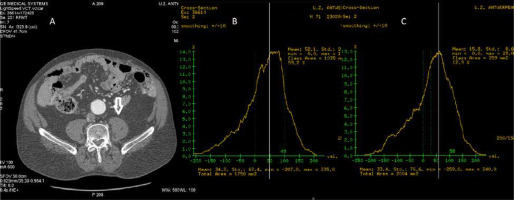

FIGURE 2

Measurements of the psoas muscle area (PMA) and muscle quality. Panel A shows the manual contouring of the region of interest (ROI), being the right PMA. Panel B: Within the ROI, a filter selects all voxels with a CT attenuation coefficient within a predefined range corresponding to skeletal muscle. Similarly, the filter can also select all voxels within the ROI with a CT attenuation value attributed to the low-density muscle (LDM). In this case, LDM was defined as the PMA portion with a CT-attenuation coefficient ranging from 0 to 29 Hounsfield units

Step 2: Determine the region of interest (ROI) by manually contouring the PMA or SMA [30] (Figure 2 Panel A).

Step 3: A filter selects the voxels with CT attenuation coefficients attributed to skeletal muscle within the ROI. A filter setting with a threshold range of – 29 to 150 HU is commonly used to define the muscle [31]. However, many researchers have used other filter settings (e.g., the muscle was defined as vo-xels with CT attenuation coefficients ranging from 0 Hounsfield units (HU) to 100 HU, within the ROI) [30] (Figure 2 Panel B).

Step 4: The CT attenuation coefficients of all voxels attributed to skeletal muscle (Step 3) are averaged. This variable is usually called HUAC (Hounsfield Units Attenuation Coefficient), PMHU (psoas muscle Hounsfield units), and psoas muscle density (PMD) in the medical literature.

Step 5: Fatty infiltration due to muscle degeneration will reduce the HUAC, as adipocyte tissue has a CT attenuation coefficient ranging from –190 to –30 HU. Thus, lower psoas muscle HUAC represents lower skeletal muscle quality. Alternatively, muscle quality can be assessed by dividing the PMA or SMA into low-density muscle (LDM) and high-density muscle (HDM) by selecting the voxels, with a predefined CT attenuation coefficient range for LDM and HDM, within the ROI (Step 2) (Figure 2 Panel C) [30]. The different approaches of muscle quality quantification are discussed in the section below.

Muscle quality. Besides quantification of the PMA, the psoas muscle CT-attenuation coefficient can also be measured, allowing qualitative skeletal muscle assessment. In myosteatosis, fatty infiltration will reduce the average psoas muscle attenuation coefficient, as adipocyte tissue has a CT attenuation coefficient ranging from –190 to –30 Hounsfield units (HU). In part 3A, we described how CT attenuation filters select the voxels representing skeletal muscle by setting the filter range from 29 HU to 150 HU [31] or from 0 HU 0 to 100 HU [30], depending on the definition of muscle. Similarly, the psoas muscle can be divided into low-density muscle (LDM) by selecting the muscle voxel with low CT attenuation coefficient (e.g., CT attenuation coefficients ranging from 0 to 29 HU, and high-density muscle (HDM), by using a filter setting, selecting the voxel with a CT attenuation coefficient ranging from 30 HU to 100 HU) [30] (Figure 2, Panel C).